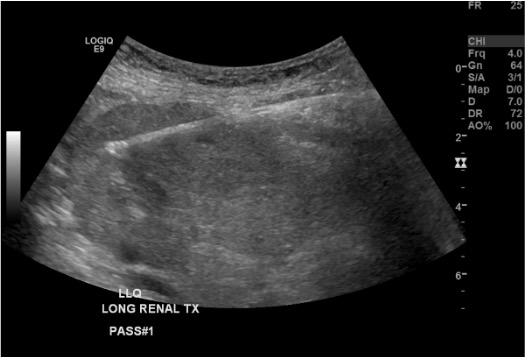

View needle in cortex

Ultrasound showing needle positioned tangentially in renal cortex during transplant biopsy